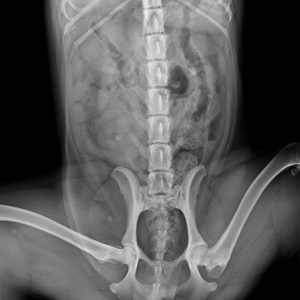

Füli kutyusunk egy jelenleg kb másfél éves, mentett, bántalmazott keverék, szuka kutyus (15 kg-os, vékony testalkatú, közepes magasságú, rövidszőrű keverék kutyus). Sérülése egy korábbi bántalmazásból eredt, mikor kiskutyaként husánggal úgy megverhették, hogy combnyaktörése lett. Ezt mi derítettük ki, mikor hozzánk került tavaly októberben. Akkor észrevettük, hogy aggasztóan sántít, és elvittük megröntgeneztetni. Több orvos véleményét is kikértem, és mindannyian azt tanácsolták, hogy műttessük meg (elég drasztikus műtéttel, a combcsontfej egy részét kivágták volna).

Molnár doktor úr egyedüliként, a röntgen kép alapján, arra bíztatott, hogy mivel a kutyus még növekedésének vége előtt állt, próbáljunk ki egy 3 hónapos csont- és porcépítő csomagot. Így is tettünk. Már kezdetben is nagy javulást észleltünk. Pár hét után el-elmaradozott a sántítás és szép lassan teljesen elmúlt. De természetesen nem elégedtünk meg ennyivel. Májusban az ivartalanítási műtét során kértem az orvost, hogy készítsen röntgenfelvételt Füli lábáról. A röntgen el is készült, és nagy örömünkre, már ez az állatorvos is azt mondta, hogy nincs szükség a combcsontfej műtétjére.